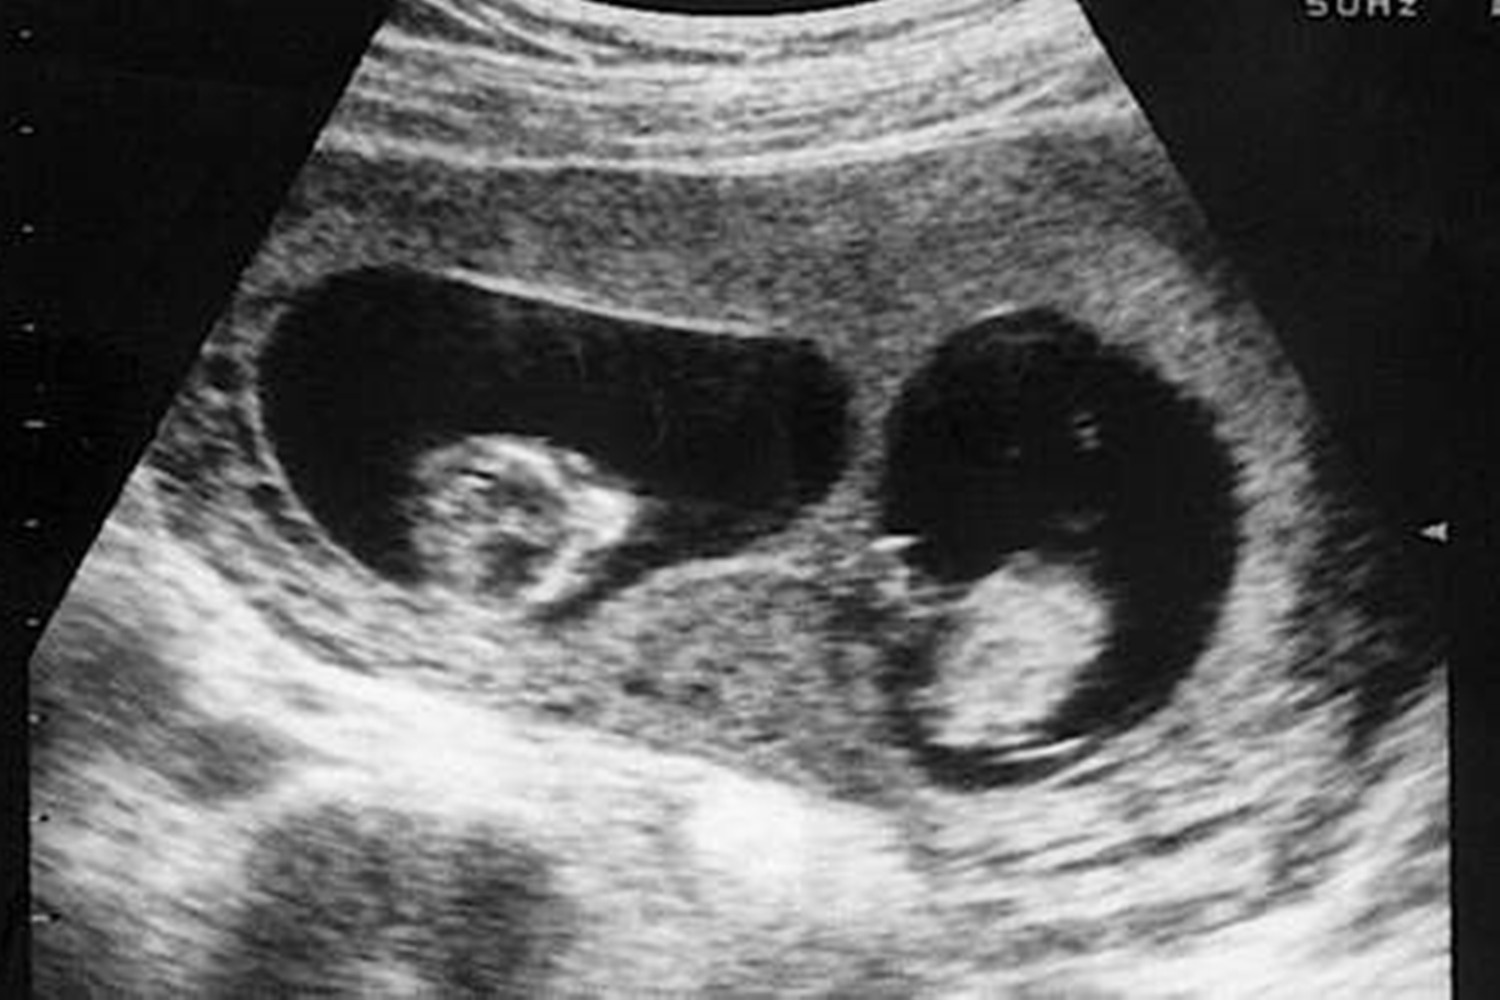

这位母亲今年28岁,在怀有双胞胎之前生了4个孩子。在检查过程中,医生说腹部有两个胚胎,怀孕的母亲和她的家人听到这个消息时心情很好。但是,很快就迎来了一个转折点。后来,在产前检查中,纪文斯检查了B超图像,发现两个胎儿的发育有很大差异,姐姐虚弱,弟弟健壮。医生很遗憾地告诉她:目前我们只能听到一个胎儿的心音,无法接受这个结果的吉恩斯去了其他医院重复检查了几次,但结论仍然是一样的。

在怀孕的第13周,医生检查后说,超声图像显示腹部只有一个胎儿,另一个已经死亡并被吸收。听到这个消息,吉文斯伤心了好几天,并且还给这位未成年的妹妹命名,以示对他的纪念和深爱。幸运的是,最后,弟弟出生得很健康。使她感到惊讶的是,当护士把婴儿抱给她时,她还向她指出了腰果状的胎记,形状和“被吸收的”结节。B超检查的图像非常相似。Givens感到既惊讶又安慰,认为这可能是他未出生的妹妹留给弟弟的特殊回忆。他弟弟出生后腿上的胎记引起了很多关注。对于这一奇妙的巧合,网友评论道: